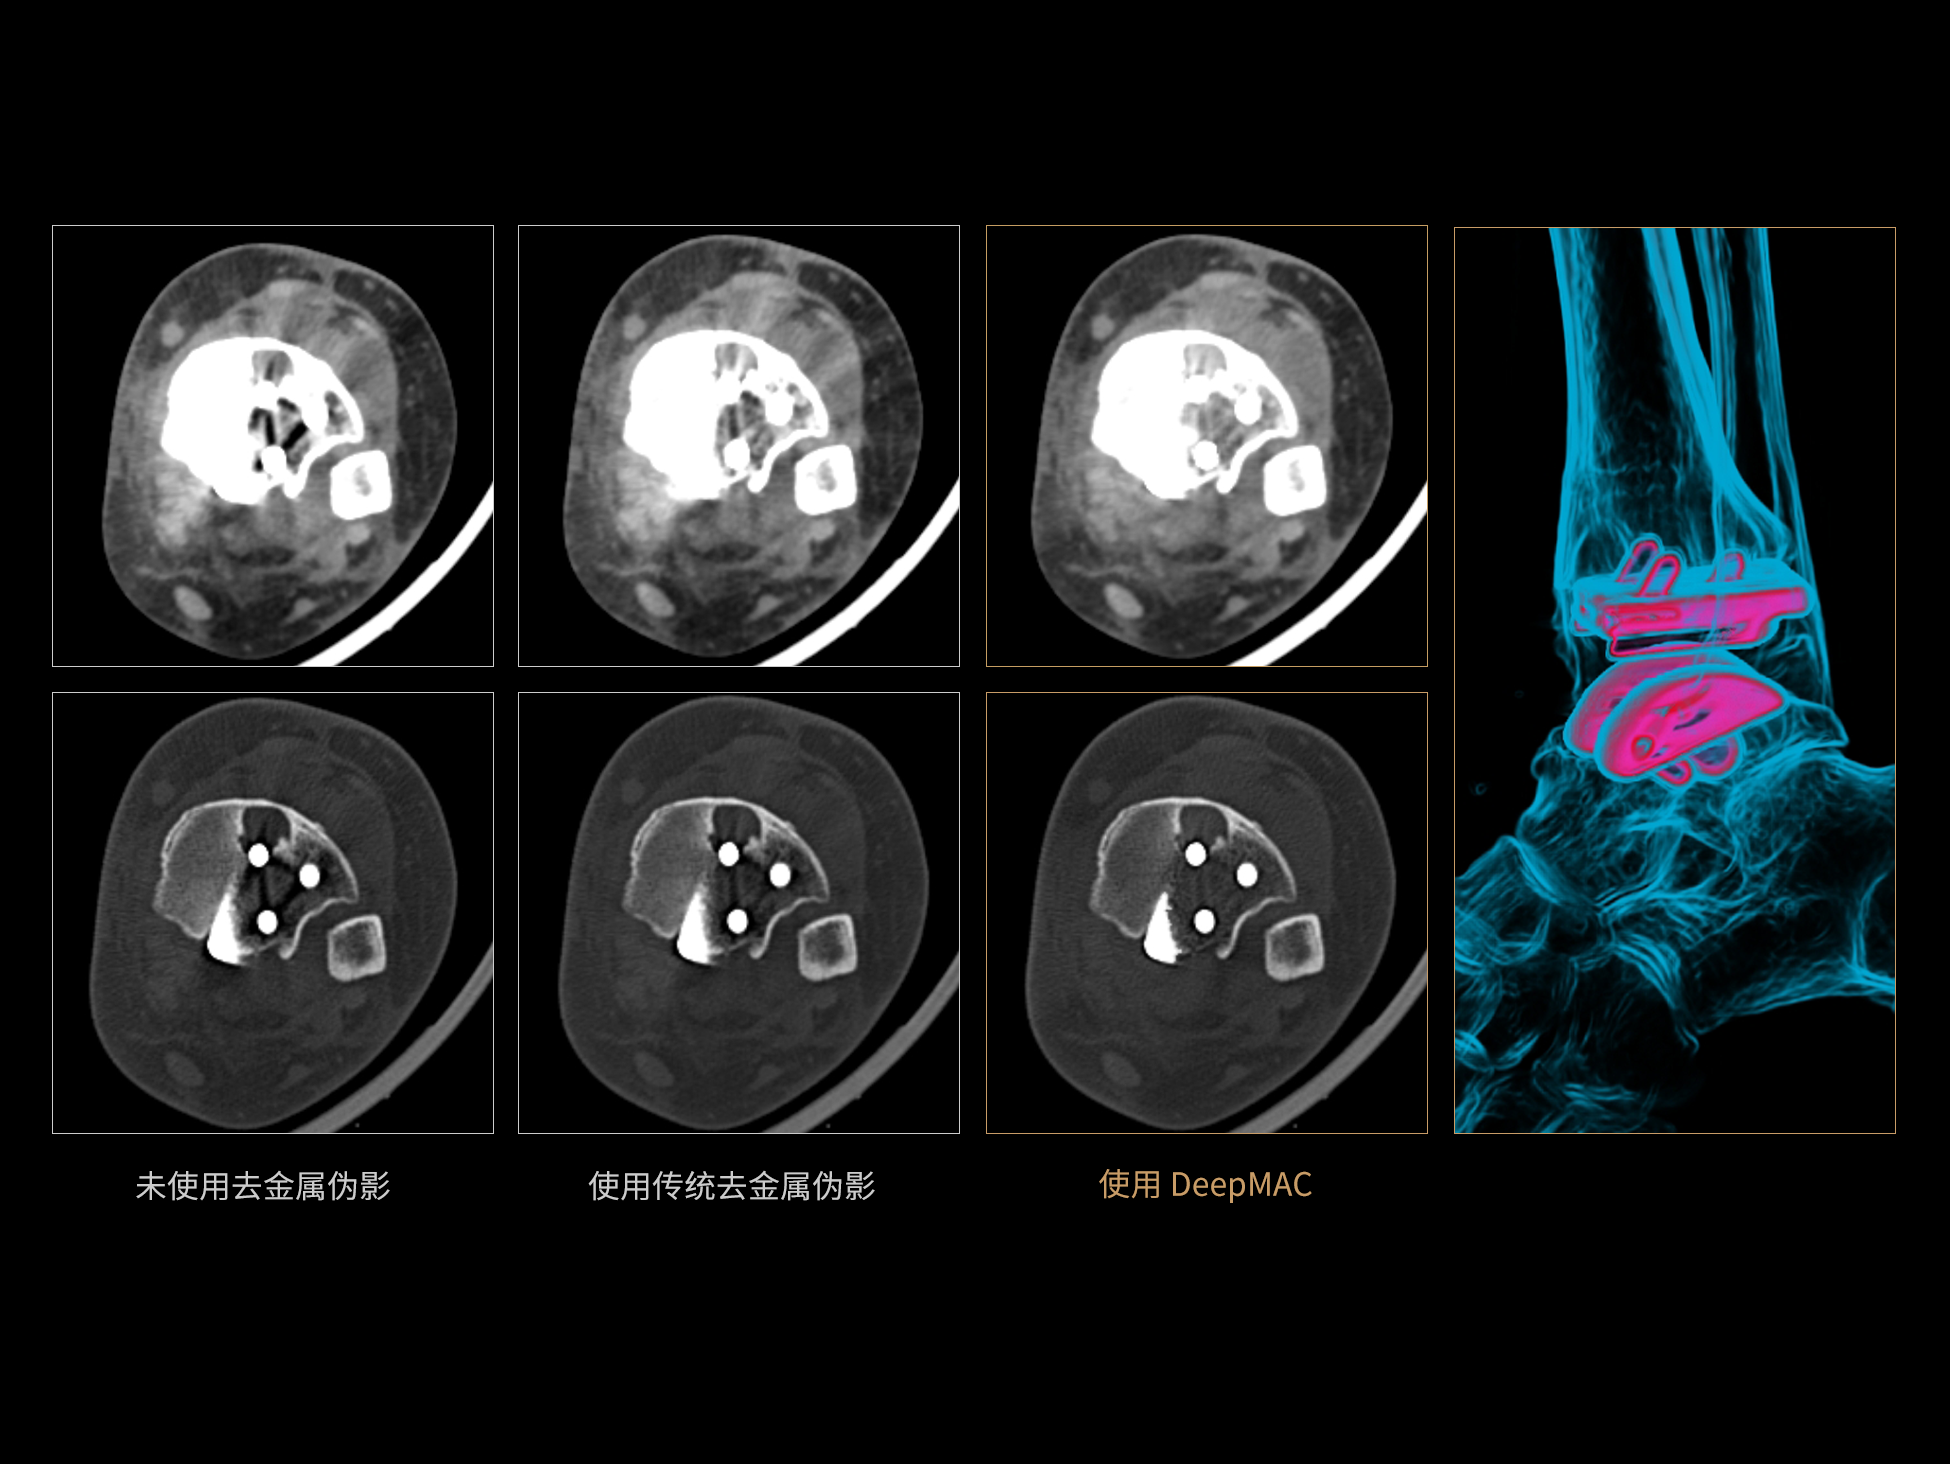

DeepMAC**:AI去金属伪影算法

DeepMAC**智能金属伪影校正技术通过深度学习算法有效解决了临床中各类不规则金属植入物导致的CT成像伪影问题,具备良好的通用性和稳定性。该技术依托大规模、高多样性的训练数据集,覆盖了包括髋关节置换体、脊柱内固定器(胸腰椎/颈椎)、四肢骨科植入物、牙科修复体以及血管介入弹簧圈等在内的金属植入物类型。通过深度神经网络的特征提取与解剖结构重建优化,DeepMAC** 在有效抑制金属伪影的同时,最大程度地保留了真实的解剖细节,显著提升了影像诊断的准确性。

±10HU

CT值准确性※ ※

≥50% 重建速度提升

相较传统算法,重建速度提高50%以上※ ※

※ ※数据在测试条件下,与传统MAC去金属伪影算法对比获得